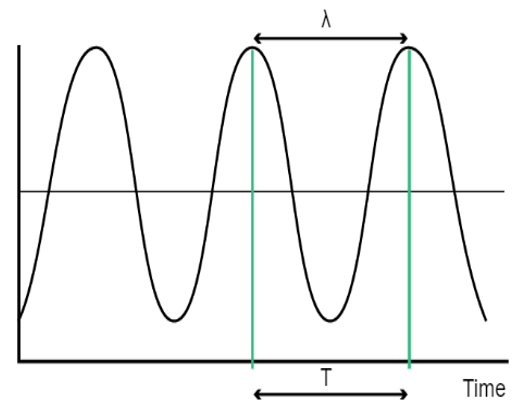

Wavelength

The wavelength is the distance traveled by the sound during a single cycle, or between two identical points in the cycle of the wave. It is the distance between two points of compression peak that follow one another. Please note that the frequency and the wavelength are inversely proportional, when the frequency increases, the wavelength decreases, and vice versa.

The wavelength (l) and the frequency (f) are connected by the below formula: